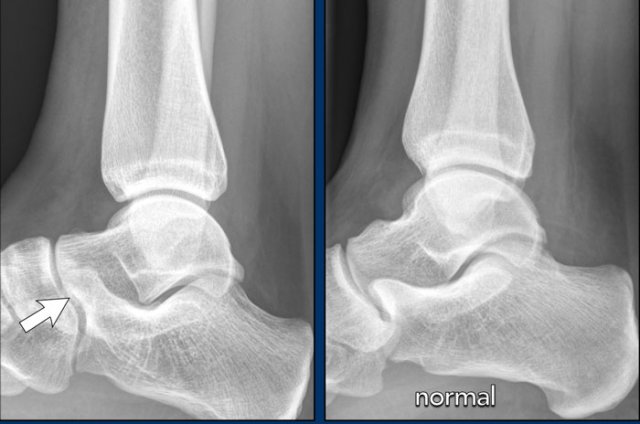

case 2 - chronic pain post ankle sprains

The findings are:

• elongated anterior process of the calcaneus that articulates with the navicular bone.

• the diagnosis is calcaneonavicular coalition.

The calcaneus and navicular bone do not normally articulate.

With osseous coalition, a bony bar that bridges the two bones is seen.

Compare to the normal situation.

With fibrous or cartilaginous coalition, the bones are in close proximity, both have irregular surfaces, and the anteromedial calcaneus is abnormally widened or flattened.

On lateral radiographs, elongation of the anterior dorsal calcaneus may simulate an anteater’s nose.